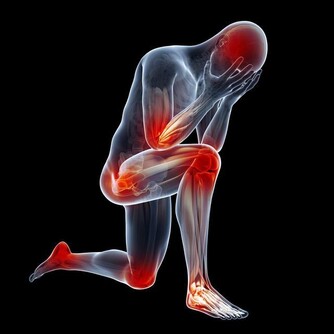

談到心肌梗塞,大家總是把這個好發於寒冷季節的疾病,跟年長的男性聯想在一起。

根據研究,女性罹患心肌梗塞的症狀其實和男性並不相同,以致於很容易被忽略而失去了搶­救的先機。

到底兩性有哪些不同的症狀?

還有,心肌梗塞一定都是突然發作的嗎?

我們能不­能從外表找到發病的前兆呢?

答案當然是肯定的,但是要怎麼看呢?